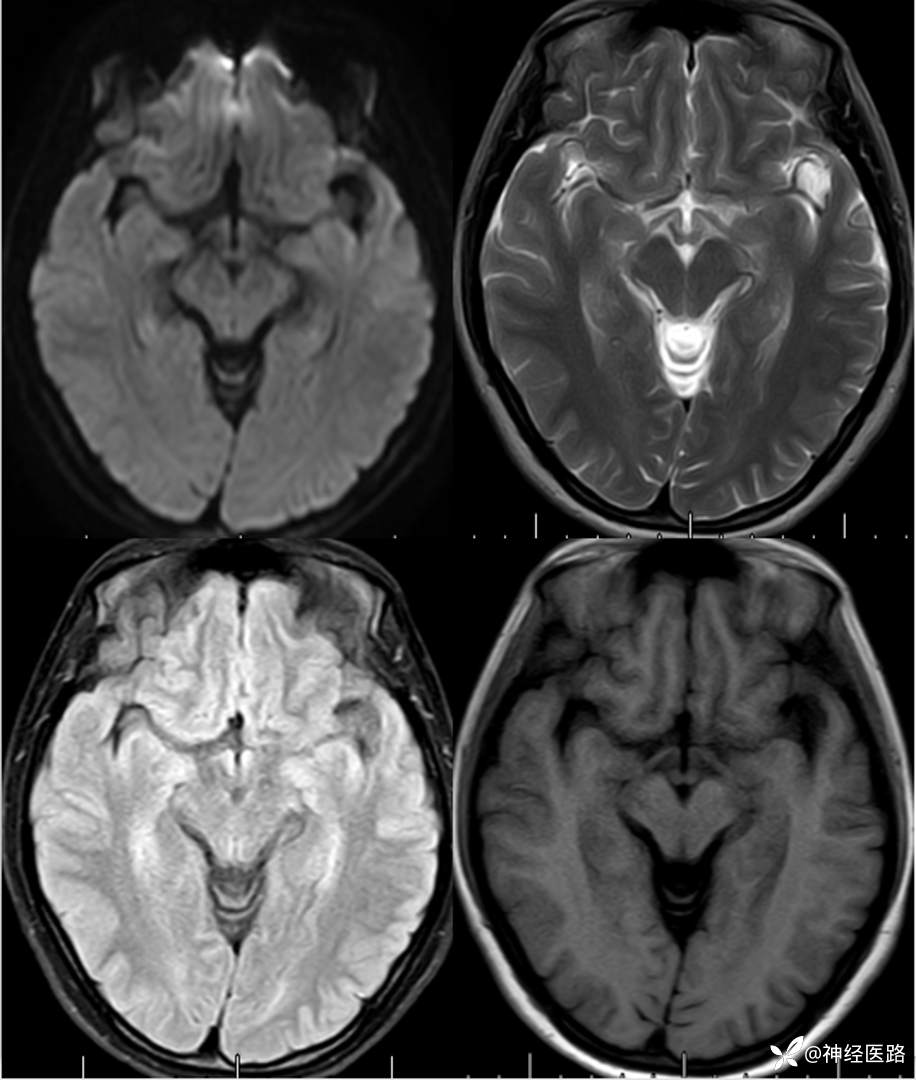

辅助检查:头部磁共振: 1.左侧额叶及右侧顶叶白质内高信号,请结合临床及相关检查。2.双侧小脑半球脑萎缩。3.部分颅骨信号增高。